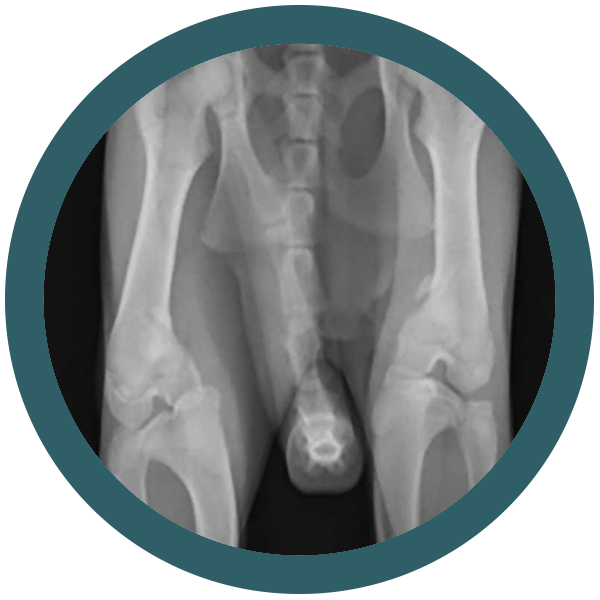

Come riconoscere una displasia dell’anca nel gatto

Osteocondrodisplasia Scottish Fold: quando la dolcezza delle orecchie nasconde un problema serio